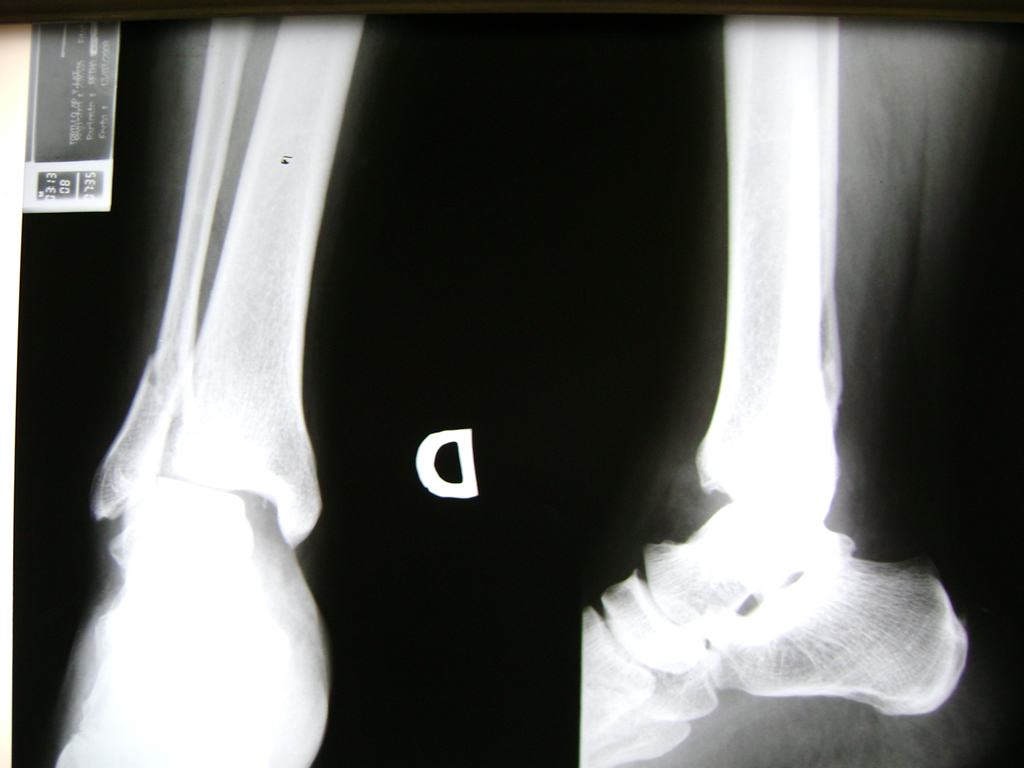

Una fractura de tobillo es la rotura de uno o más de los huesos del tobillo. Estas fracturas pueden ser:

- Parciales (el hueso está sólo parcialmente fisurado, no del todo).

- Completas (el hueso está perforado y está en 2 partes).

- Producirse en uno o ambos lados del tobillo.

- Los extremos de los huesos están desalineados entre sí (desplazados).

- La fractura se extiende hasta la articulación del tobillo (fractura intra-articular).